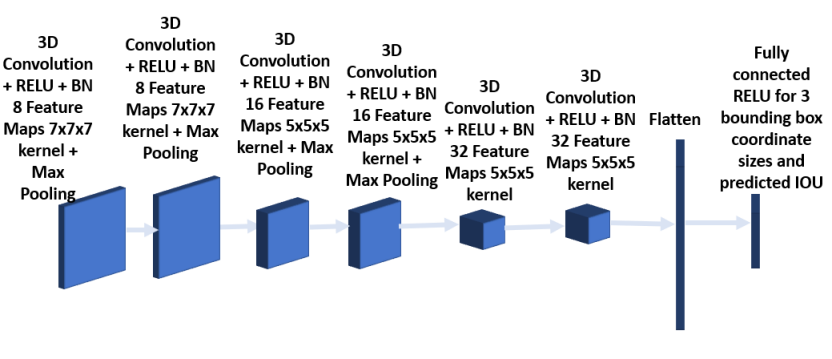

To improve overall performance, two other CNN architectures were trained besides the one described above, and the predicted bounding boxes using all three models are provided to the next stage for analysis. The architecture of the second model consists of 6 convolution layers as shown in Figures 7 and 8 respectively. The first 2 layers have kernel size 7x7x7, followed by 2 convolution layers with kernel size 5x5x5 and the final 2 convolution layers having kernel size 3x3x3. Each convolution layer is followed by batch normalization. Max pooling is added after the second and fourth layer. The third model as shown in Figures 9 and 10 has a convolution layer with 9x9x9 kernel and a batch normalization preceding the architecture in the model shown in Figures 5 and 6.